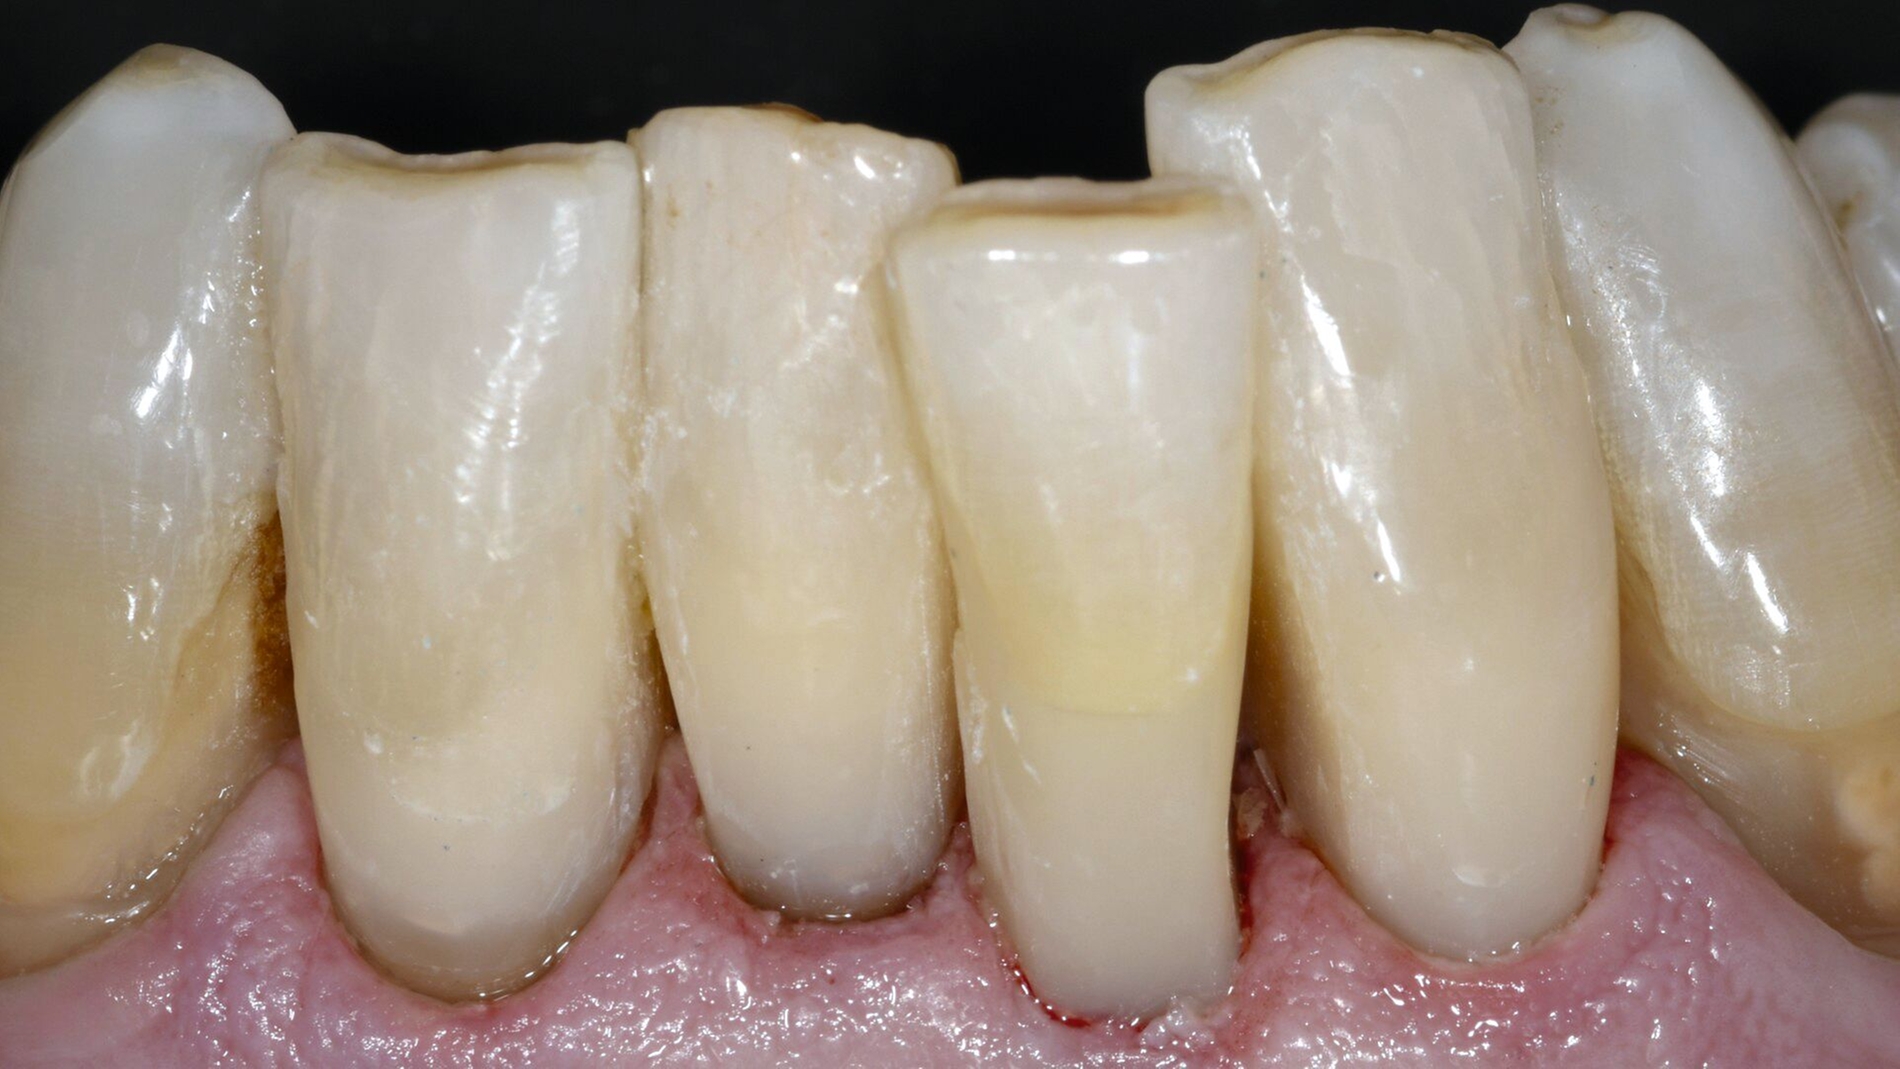

Ein sich seit vielen Jahren bei mir in Behandlung befindlicher 75-jähriger Patient klagte zunehmend über Hypersensibilitäten an den unteren Frontzähnen, die im Zahnhalsbereich ausgeprägte Zahnhartsubstanzdefekte aufwiesen (Abbildungen 1a–1d). Die Mundhygiene wurde als gut eingestuft. Möglicherweise waren die vorliegenden Zahnhalsdefekte als sogenannte Putzdefekte zu klassifizieren, wie sie bei intensiven Mundhygienebemühungen häufig zu beobachten sind.

Mit zunehmendem Alter hatte der Patient allerdings Mühe, die schwer zugänglichen Defekte adäquat zu reinigen. Zudem musste man befürchten, dass es bei weiterem Abbau der Zahnhartsubstanz in diesen Bereichen zu einem Verlust der Zahnintegrität oder einer Pulpaexposition kommt. Daher wurde entschieden, die besonders stark betroffenen Zähne 31, 32, 41 und 42 mit Kompositrestaurationen im Zahnhalsbereich zu versorgen.

Die Zähne reagierten positiv auf einen Sensibilitätstest mit Kältespray und wiesen Sondierungstiefen von 2-3 mm Tiefe auf. Die Zähne wurden wie nachfolgend beschrieben versorgt. Nach fünf Jahren Beobachtungszeit sind die Restaurationen des nun 80-jährigen Patienten bis auf kleine Defekte im zervikalen Anteil als akzeptabel einzustufen. Die Gingiva weist eine über die Beobachtungszeit leicht progrediente Rezession auf.